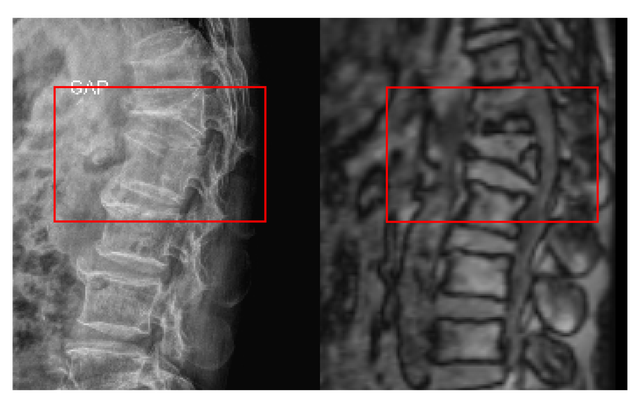

Sau thăm khám lâm sàng kết hợp chẩn đoán hình ảnh bằng MRI, BS.CKII Lê Trọng Nghĩa – Phó Trưởng khoa Ngoại Thần kinh – Cột sống, Bệnh viện Đa khoa Quốc tế Nam Sài Gòn xác định ông T. bị gãy xẹp đốt sống thắt lưng L1 trên nền loãng xương, có liên quan đến tai nạn trước đó.

Tổn thương khiến cột sống mất đường cong sinh lý, dần hình thành gù lưng và làm hạn chế khả năng vận động. Tình trạng này cho thấy điều trị bảo tồn giờ đây không còn phù hợp, người bệnh cần được can thiệp phẫu thuật sớm để ngăn ngừa nguy cơ suy giảm vận động và phụ thuộc dụng cụ hỗ trợ trong tương lai.

Đốt sống L1 của ông T. bị xẹp lún và tình trạng gù lưng có thể dễ dàng nhận thấy qua phim chụp MRI và X-quang